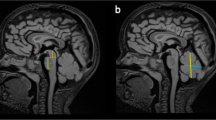

Fetal and postnatal imaging

Upward rotation of cerebellar vermis in Dandy Walker malformation

We studied the histopathology of a total of 31 cerebellar malformation cases between 15 and 34 post-conception weeks (pcw) from multiple centers (Suppl. Fig. S1, 2; Suppl. Table S1; online resource). Centers independently diagnosed 26 cases as DWM and 5 as CVH following an initial ultrasound followed by fetal MRI, with diagnosis confirmed by pathology. For 6 DWM cases we obtained imaging files and performed morphobiometric analyses of the cerebellum, measuring: a) vermian antero-posterior diameter (APD), b) vermian cranio-caudal diameter (CCD) and c) the tegmento-vermian angle (TVA), as defined previously [11, 35] (Fig. 1d–f; table). The vermian APD and CCD for all of the cases studied was below the 5th percentile, while the TVA was wider in all cases indicating that the cerebellar morphobiometry of our cases deviated significantly from normal [11, 35].